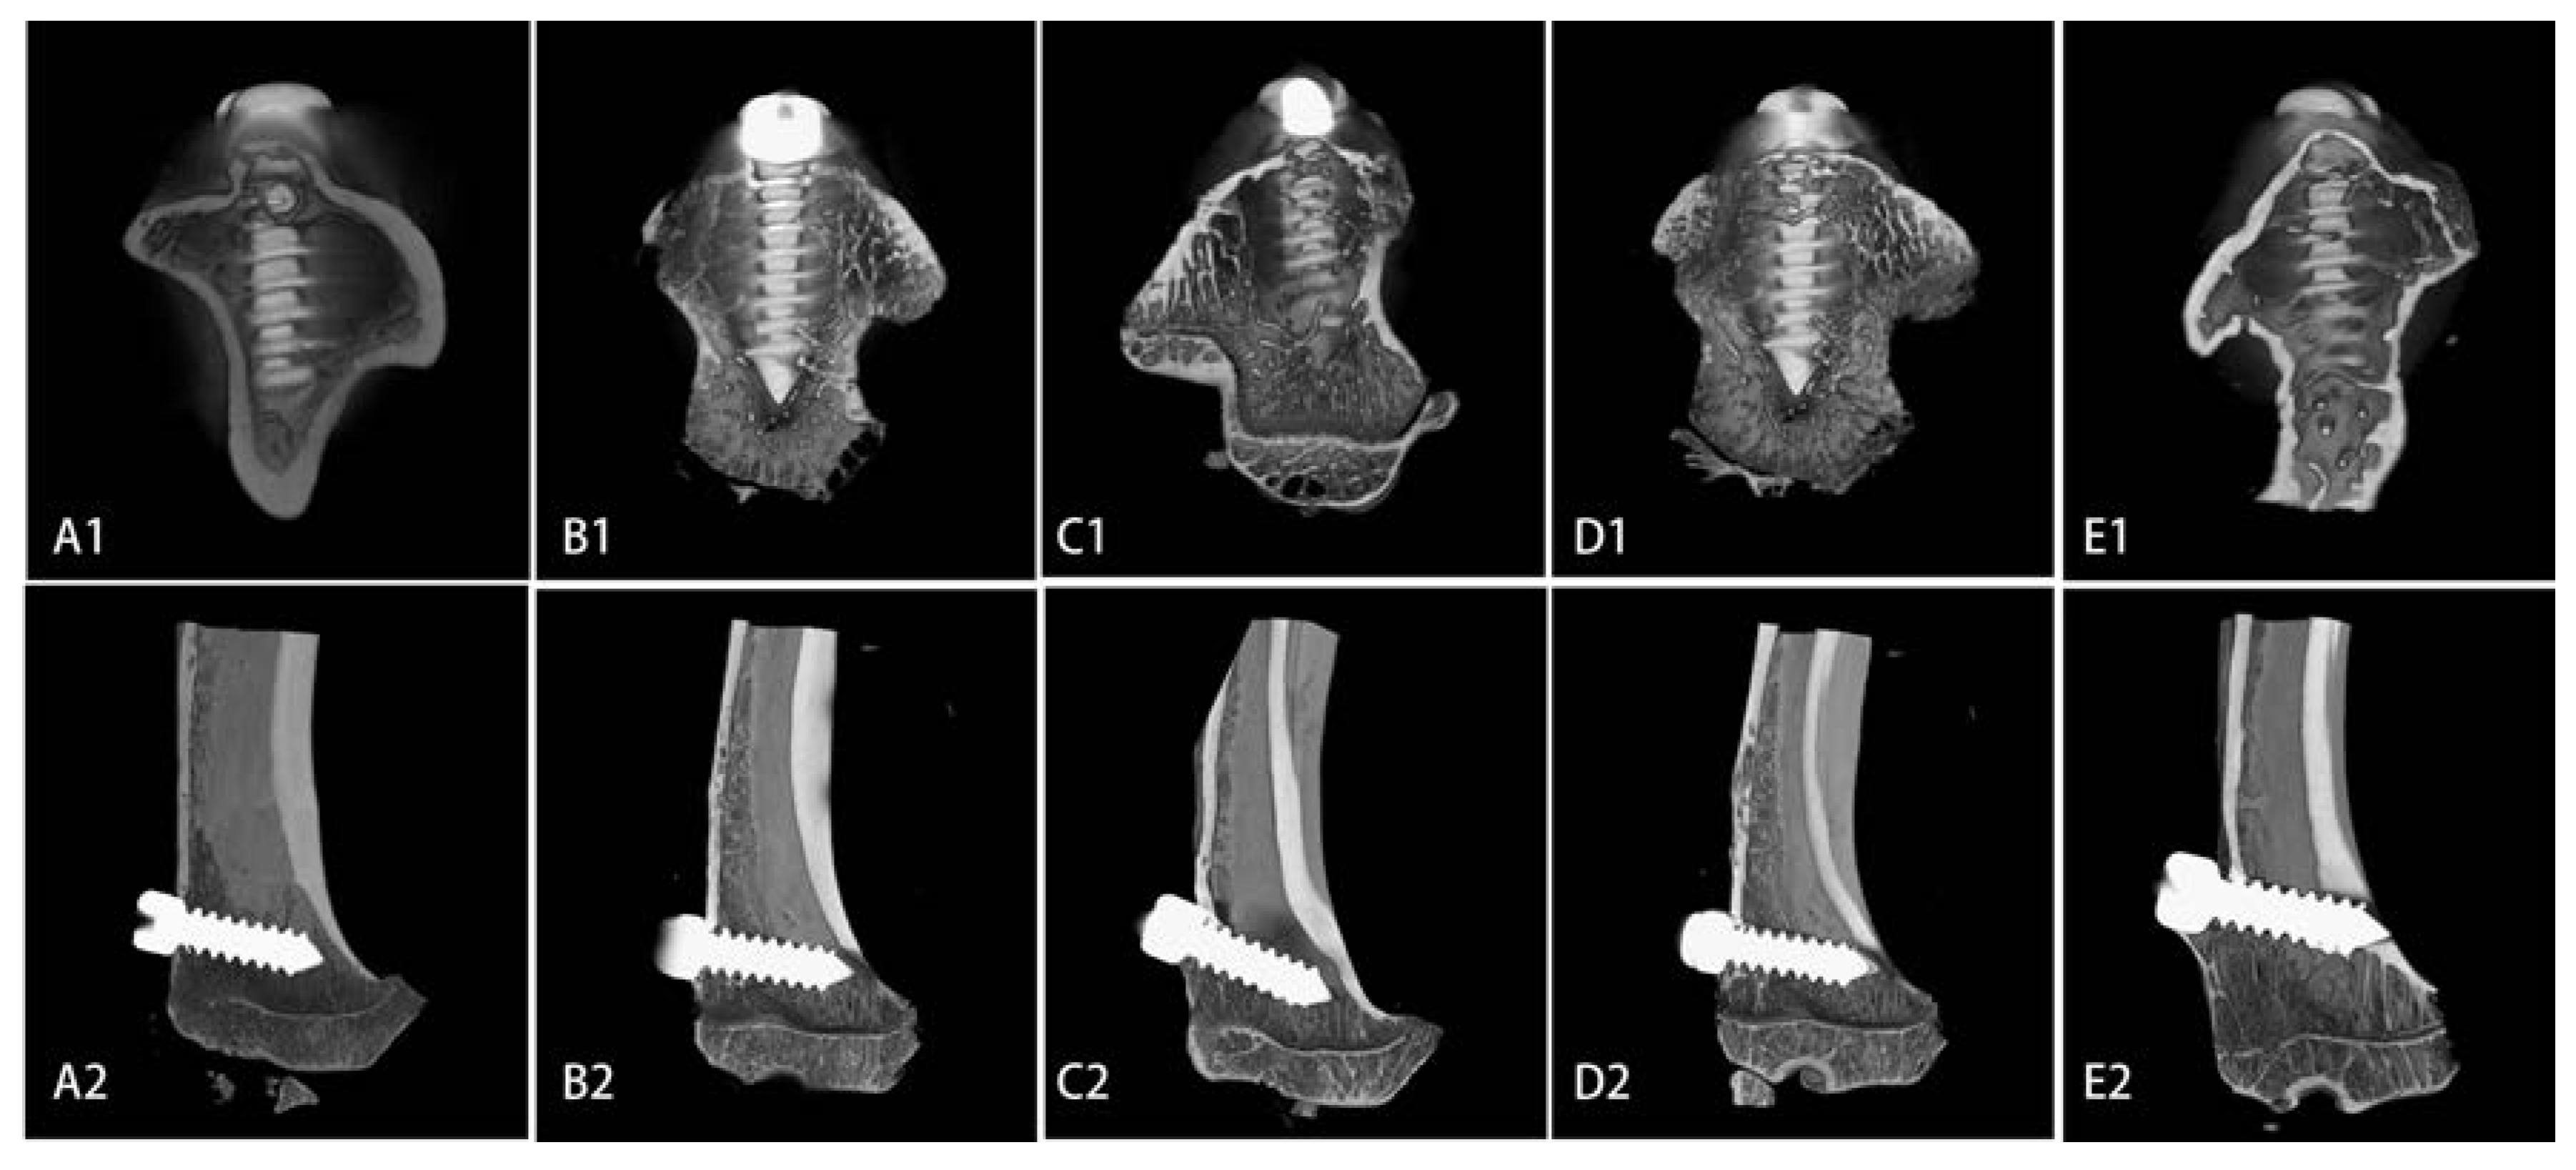

2.4. Microarchitecture of Bone Formed Around Sr-Doped Brushite-Coated Ti Implants